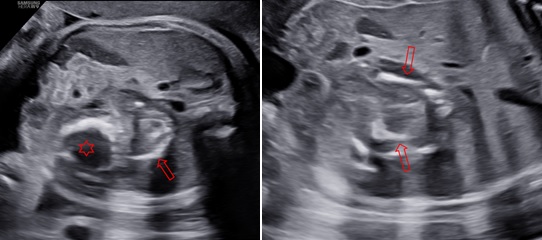

Siêu âm ngã bụng với máy HERA W9 (Samsung) ở các thời điểm 31 tuần 4 ngày, 34 tuần 3 ngày và 39 tuần. Ở hạ sườn trái và cực trên của thận trái có một khối không đồng nhất với kích thước tăng theo tuổi thai lần lượt là: 45x50x42mm, 48x58x50mm và 80x74x66mm. Bên trong khối này thấy hình ảnh vôi hoá có dạng của xương vòm sọ, xương đùi, xương sống và hình ảnh các cấu trúc này rõ khi tuổi thai lớn hơn. Trên Doppler màu, có một mạch máu nuôi khối này xuất phát từ động mạch chủ bụng của thai vật chủ với dạng sóng của động mạch rốn.

Hình 1: Thai 31 tuần 4 ngày, mặt cắt ngang và dọc bụng thai cho thấy một khối không đồng nhất nằm ở vùng hạ sườn trái dưới cơ hoành (hình tròn), đẩy thận trái xuống dưới (hình mũi tên).

Hình 2: Thai 34 tuần 2 ngày, mặt cắt ngang và dọc bụng cho thấy trong khối này có các cấu trúc giống vòm sọ (dấu sao) và cột sống và xương đùi (mũi tên)